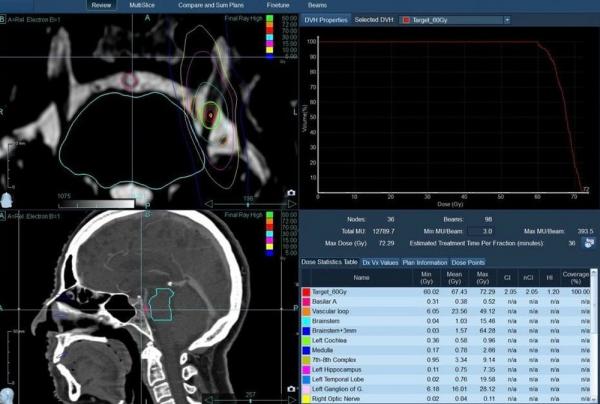

وأوضح الفيزيائي الطبي محمود الفيشاوي أن الجراحة الإشعاعية أٌجريت عن طريق توجيه جرعة إشعاعية مركزة جدًا تبلغ 6000 وحدة شعاعية في منطقة صغيرة تتراوح بين (3 ميليمترات- 6 ميليمترات) في منطقة قريبة من جذع الدماغ بمسافة لا تقل عن 3 مليمترات، مما يتطلب دقة عالية في توجيه الحزم الإشعاعية لإتلاف العصب وتقليل الألم أو التخلص منه".

وقالت إقبال العامرية الفيزيائية الطبية للعلاج بالإشعاع: إن "جهاز CyberKnifeS7 يعد من أحدث الأجهزة المستخدمة في العلاج الإشعاعي ويتميز بالدقة العالية في علاج أورام الدماغ العميقة التي يصعب الوصول إليها، وكذلك علاج الحالات غير سرطانية كألم العصب الخامس، وقد بدأنا بعلاج عدد من الحالات باستخدام الجهاز منذ منتصف شهر يناير الماضي".